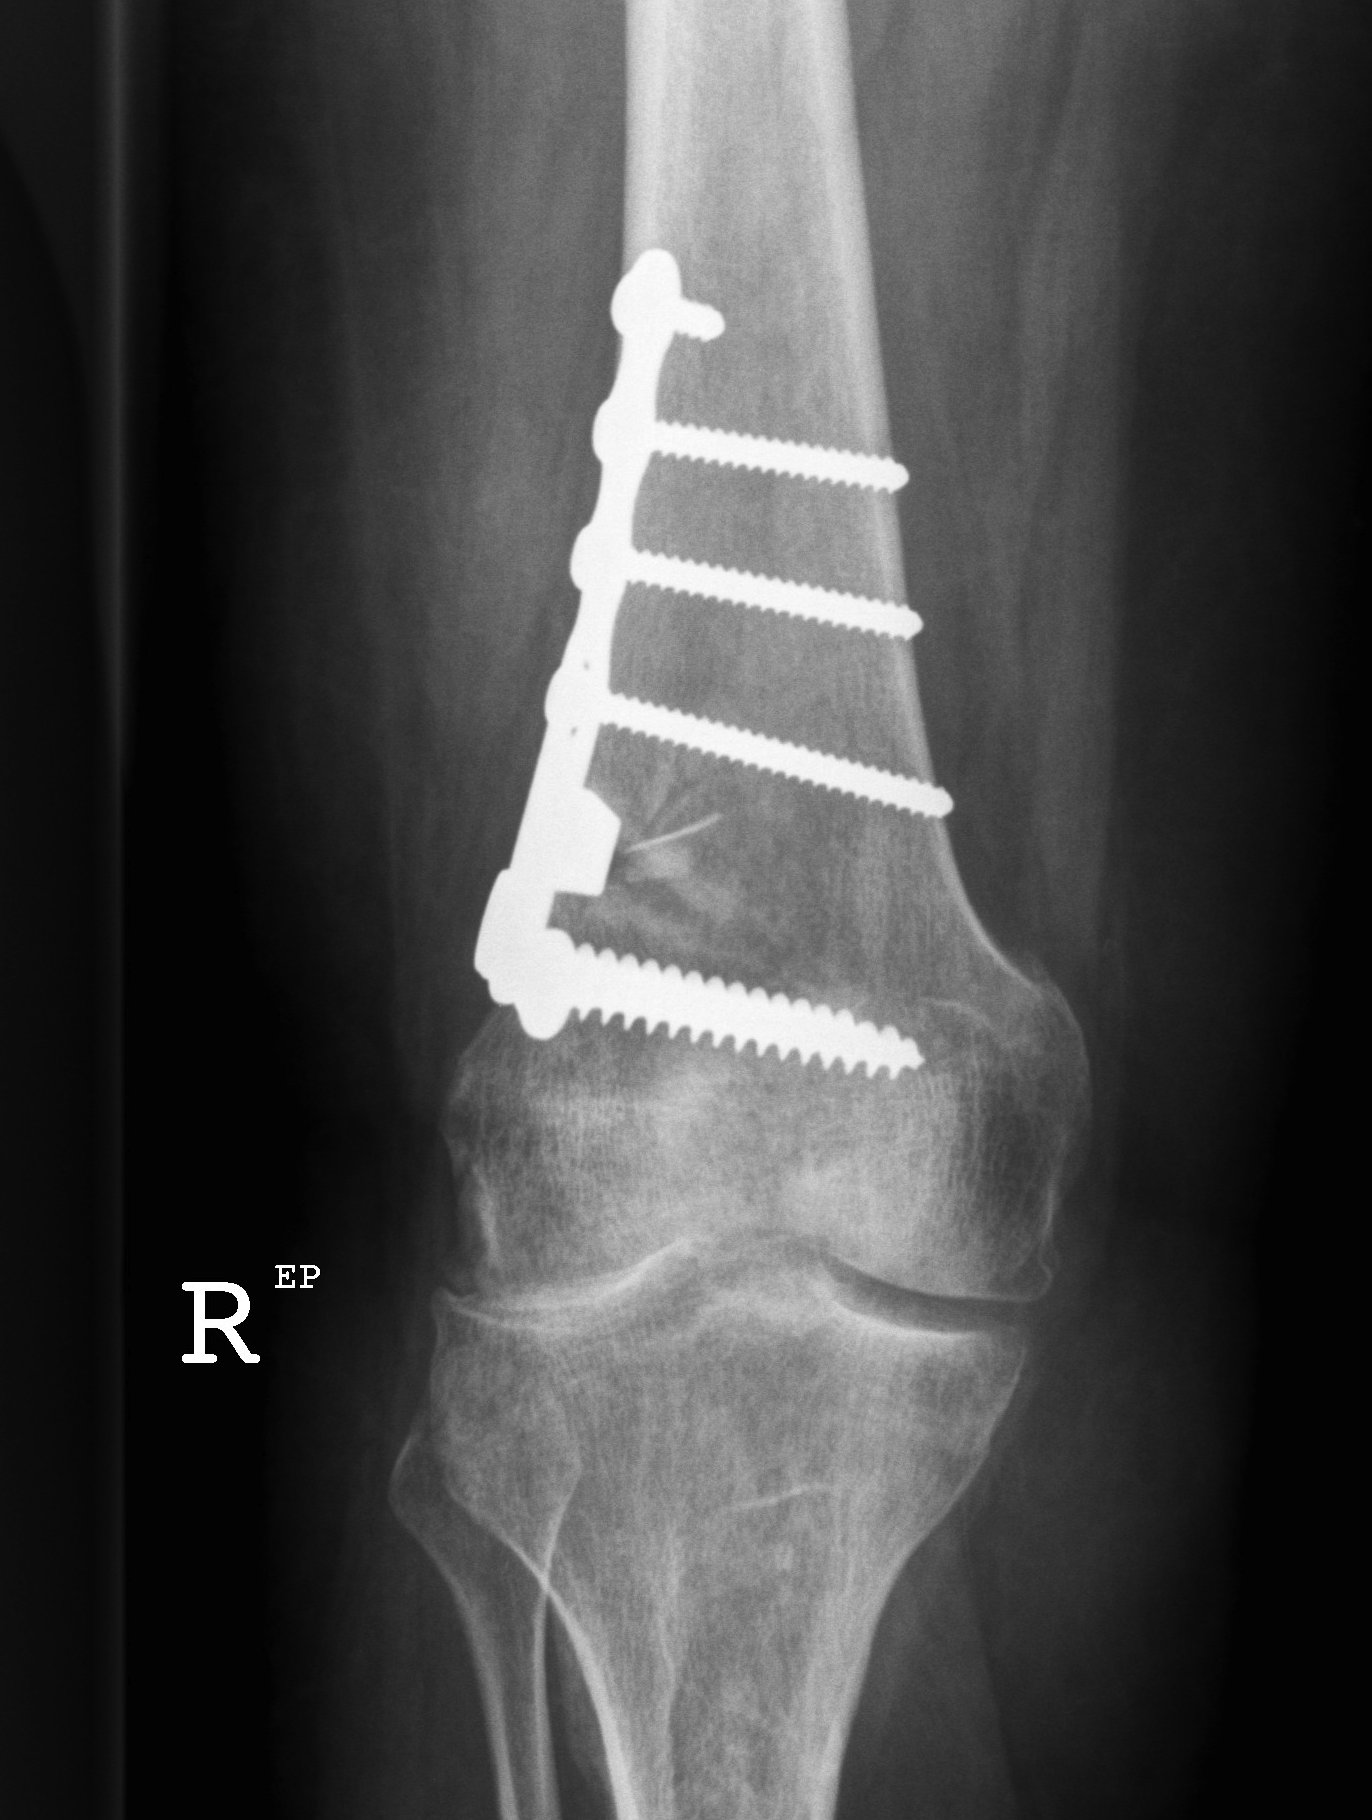

Osteotomy

- insert two K wires for desired wedge

- resect templated wedge

- stop 1 cm short of lateral cortex

- close femoral wedge